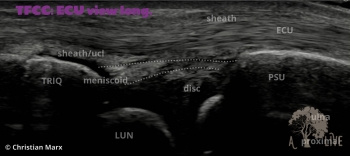

carpal ligaments